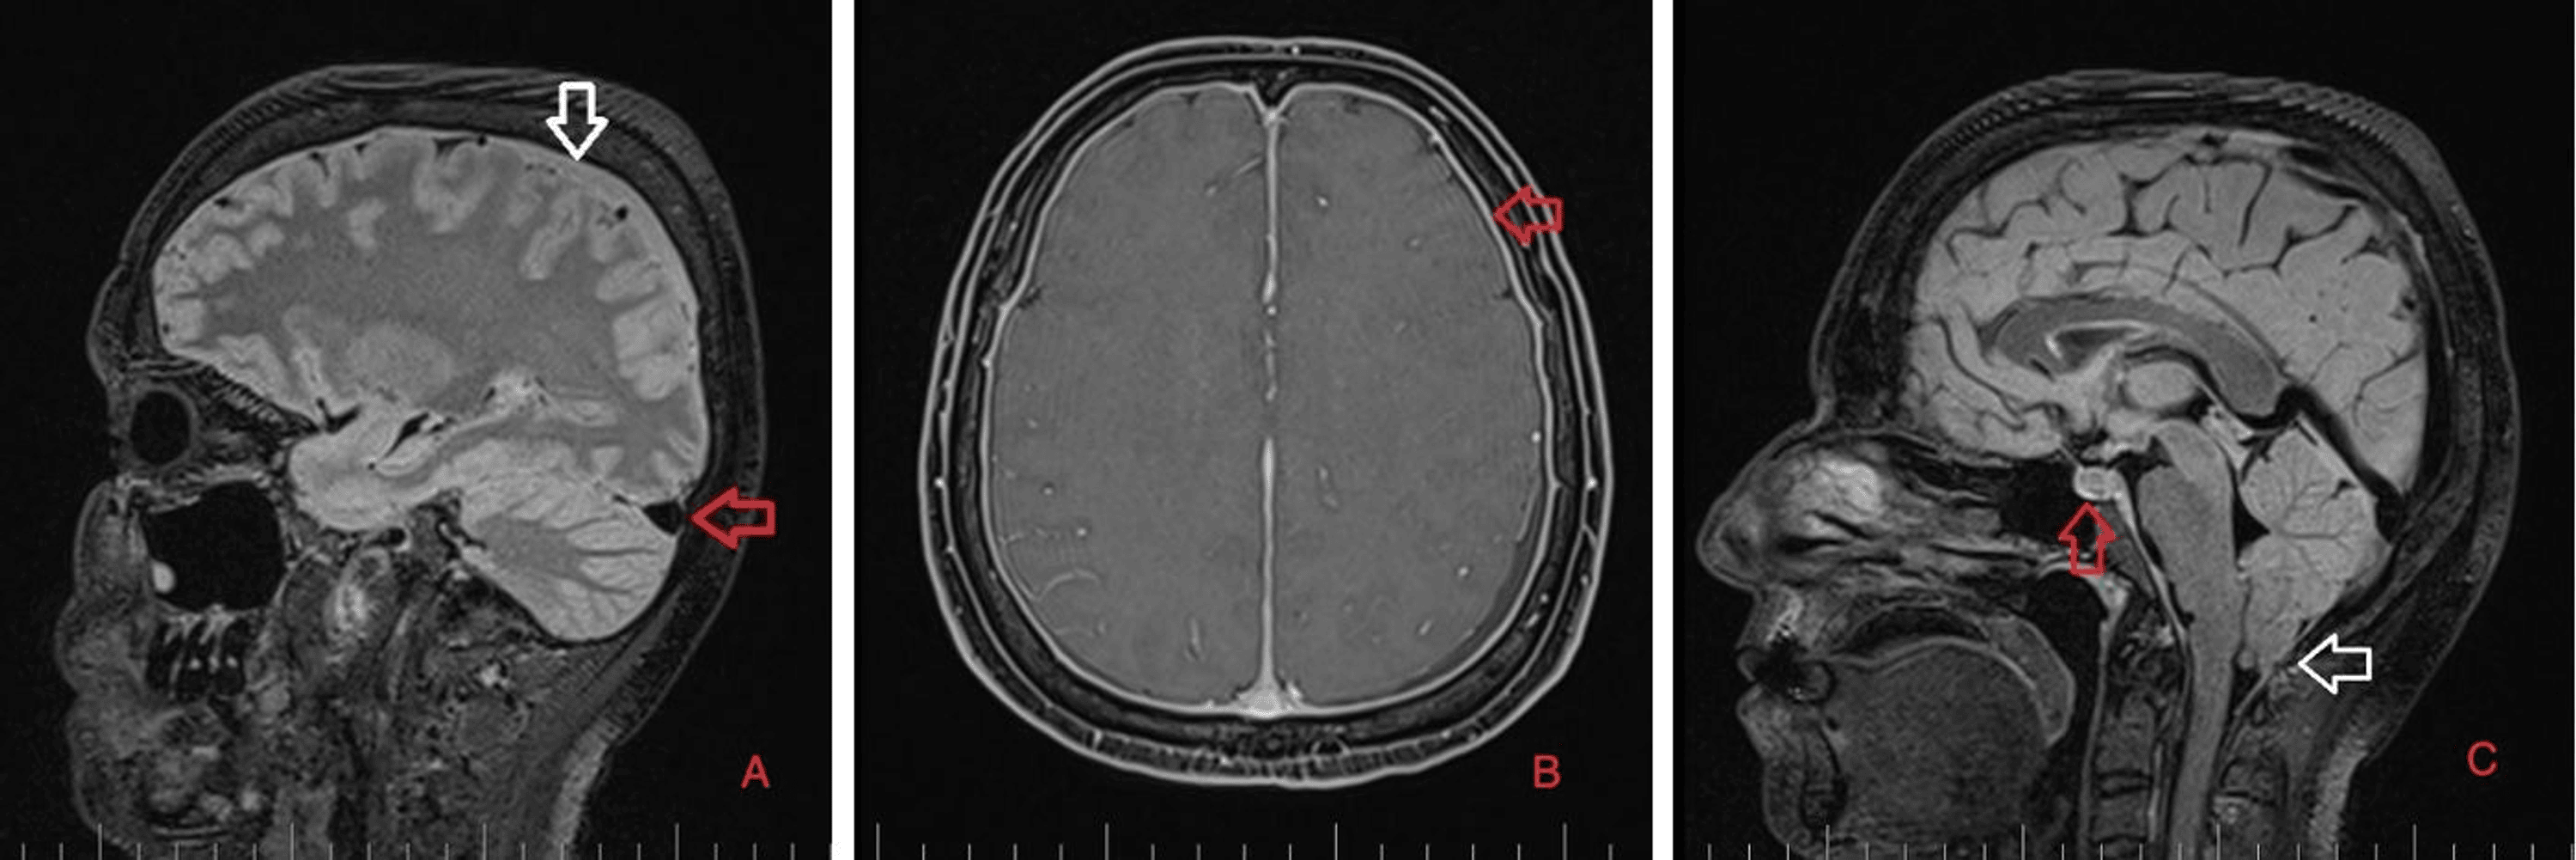

As part of the differential diagnosis, further imaging was performed. A brain MRI on February 1, 2023 (Figure 1) showed the following signs of SIH: subdural fluid collection up to 5.00 mm in the parietal area; diffuse, smooth dural thickening and pachymeningeal contrast enhancement; slightly homogeneous enlargement of the pituitary; cerebellar tonsillar descent into the foramen magnum; distension of the cerebral venous sinuses without thrombosis; and reduced fluid volume in the optic nerve sheath.

A brain and C spine MRI scan on March 5, 2023 (one month after the procedure) showed a regression of the subdural collection from 5.00 mm to 2.5 mm in the parietal area but all other parameters remained unchanged (Figure 3).

Brain and C spine MRI (Figures 5, 6) on September 4, 2023, showed a total regression of SIH signs. MRI myelography showed complete resorption of the SLEC, with no CSF leak. The patient was without any clinical symptoms or headache. She continues to work as a nurse. Her quality of life has improved significantly.

Numerous cranial MRI signs of SIH have been described. As almost all SIH cases are caused by spinal CSF leaks, spinal MRI is complementary to head scans. Some patients have spinal CSF leaks but do not show SIH signs in head scans; therefore, with appropriate clinical symptoms, both head and spinal MRI scans should be performed [2]. Dobrocky et al. described a novel scale based on MRI findings to help decide the need for invasive techniques to identify a possible CSF leak in patients presenting with postural headaches. They analyzed nine quantitative parameters and seven qualitative parameters. Enhancement of the pachymenginges, engorgement of venous sinus, and effacement of the suprasellar cistern of 4 mm or less, as major findings, were assigned a score of 2, while subdural fluid collection, effacement of the prepontine cistern of 5 mm or less, and mamillopontine distance of 6.50 mm or less were considered minor and assigned 1 point each. Patients with 5 points on a scale of 9 points or more have a high probability of having a CSF leak [11].